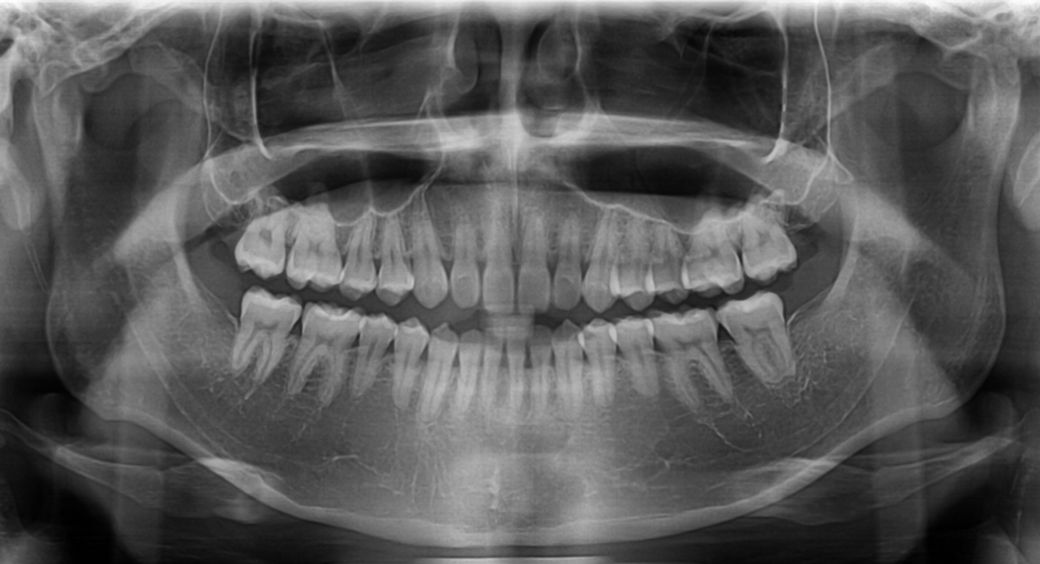

윗니가 아랫니를 덮는 양또는 윗니가 앞으로 나온양이조금 적다고는 하는데 골격적 문제라 어쩔 수 없다는데 맞나요?

부분 교정으로도 어려워 보이며 전체 교정도 현재 증상을 개선하기가 쉽지 않아 보입니다. 워낙 다른 부위에 치열 상태는 나쁘지 않기 때문에 교정을 하더라도 현재 증상에 대한 개선이 어려울 수도 있어 보입니다. 또한 치열 배열 뿐만 아니라 골격적 문제가 동반되고 있어 골격적인 부분은 교정으로 수정할 수가 없습니다.

지금 정도의 골격적 부조화는 일반인들은 알아차리지 못하며 양악 등을 수술을 권하는 정도도 아닙니다.